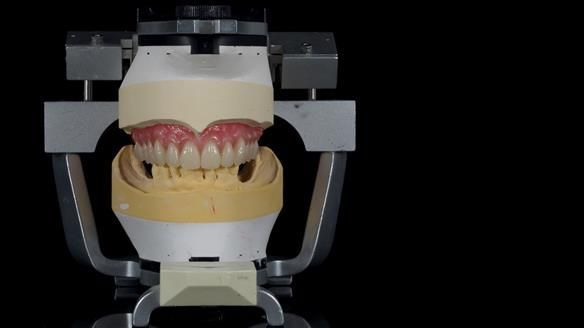

We provided her with an immediate upper denture (Mk 1), followed by a definitive metal-based upper denture (Mk 2). A lower removable partial denture was discussed, to be made only if needed once the upper treatment was complete. However, at review, this wasn’t necessary — Adnana had excellent neuromuscular control and function, even with a shortened dental arch (SDA).

Rowan, Sam Hesketh and Chris Hesketh provided the stunning technical work. I am very lucky to have them.